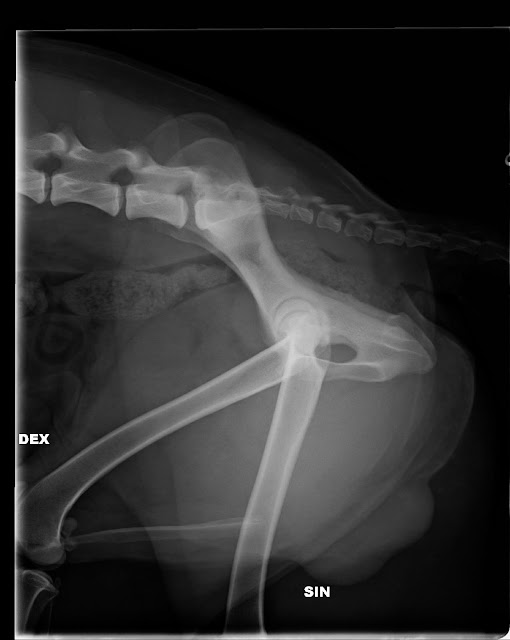

EEJW-12 FI MVA Colombo

nikamien epämuotoisuus - VA0 (normaali)

selän spondyloosi - SP0 (puhdas)

välimuotoinen lanne-ristinikama - LTV4 (6 tai 8 lannenikamaa)

T13 vajaakehittyneet kylkiluut.

L6.

Rajatapaus VA

Kuvaaja: Laura Hakala

Lausuja: Anu Lappalainen

LTV4-diagnoosi ei mitä todennäköisimmin tule vaikuttamaan meidän elämäämme mitenkään. Lonkan nivelrikko ei ole vuoden takaiseen nähden juurikaan edennyt ja mikä tärkeintä, vasempaan ei ole rikkoa kehittynyt.